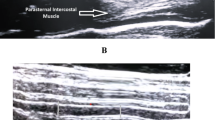

For the intercostal ultrasound, the probe was placed vertically in the parasternal region between the second and third ribs, approximately 2–4 cm lateral to the sternum. The parasternal intercostal muscle appears as a three-layered biconcave structure. Two hyperechoic membranes outline the central muscle portion. Intercostal muscle thickness was measured at end-inspiration (ITinsp) and end-expiration (ITexsp) in B-mode between the inner and outer hyperechoic fascial borders. ITF was calculated as11:

Exemplary images of DTF and ITF measurements are provided as eFigure 1 and supplemental electronic material.